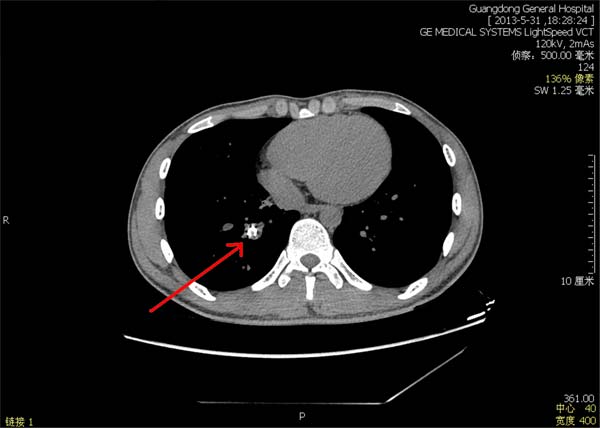

病例一:小青是一位青年男性,近10多年来常常患有肺炎,近期检查才发现是幼时支气管异物误入气道所引起的并发症。若支气管异物不取出,肺部感染仍会反复发作。然而由于异物在气道时间太长,不断刺激支气管疤痕形成,不仅导致异物所在支气管明显狭窄,而且异物已被周围组织深深包埋,异物取出难度极大,且容易出血或损伤气道(图1)。外院曾尝支气管镜检查,但未能取出异物。为此,小青转至我院就诊。呼吸科高兴林主任、吴健主任,经过认真分析,决定综合采用气道介入治疗技术来钳取异物。两位主刀医生先用高频电刀扩大疤痕狭窄的支气管,再小心烧灼分离肉芽组织,使异物处于游离状态,最后小心地将异物取出。原来是小青幼时咬笔时不慎误吸笔帽(图2),由于在体内滞留时间太长,已经明显变形、碎裂。由于精心准备及严谨操作,介入手术过程顺利,无大出血及其他严重不良反应。复查胸片及支气管镜,未见异物残留。经治疗后,小青痊愈出院。

图1:头所指为异物,已经被周围组织包埋